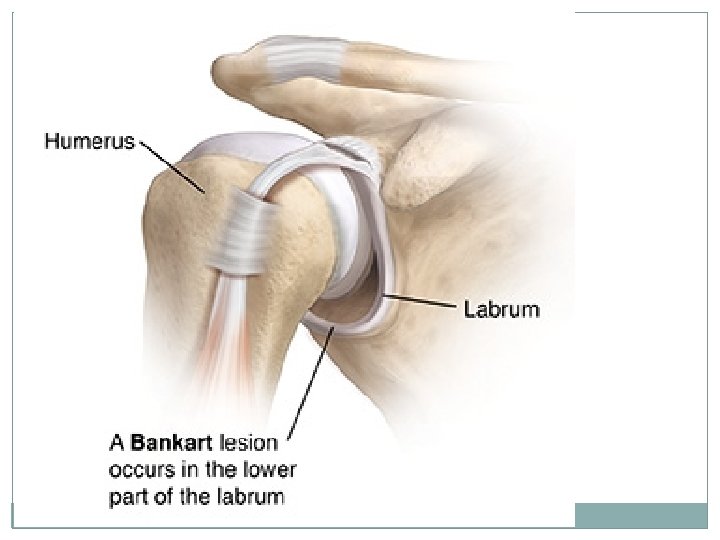

Lesions that are commonly seen with an anterior dislocation include the Hill-Sachs fracture and the Bankart fracture. A Hill-Sachs fracture is a fracture of the humeral head. It occurs along the posterior and superior aspect and is caused by the impaction of the humeral head on the inferior aspect of the glenoid process. A Bankart fracture is caused by the same mechanism, but it is a fracture of the inferior aspect of the glenoid process.

STABILITY OF THE SHOULDER JOINT 25 This joint is unstable because of the: shallowness of the glenoid fossa weak ligaments Its strength almost entirely depends on the tone of the rotator cuff muscles. The tendons of these muscles are fused to the underlying capsule of the shoulder joint. The least supported part of the joint lies in the inferior location, where it is unprotected by muscles.

DISLOCATIONS OF THE SHOULDER JOINT The shoulder joint is the most commonly dislocated large joint. 26 Anterior-Inferior Dislocation Sudden violence applied to the humerus with the joint fully abducted pushes the humeral head downward onto the inferior weak part of the capsule, which tears, and the humeral head comes to lie inferior to the glenoid fossa.